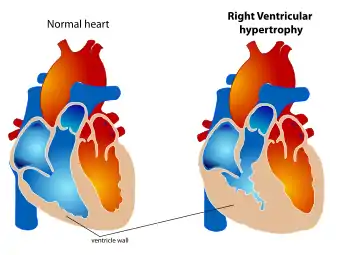

| The diagram shows a typical heart (left) and one with ventricular hypertrophy (right). | |

Ventricular hypertrophy (VH) is thickening of the walls of a ventricle (lower chamber) of the heart.[1] Although left ventricular hypertrophy (LVH) is more common, right ventricular hypertrophy (RVH), as well as concurrent hypertrophy of both ventricles can also occur.